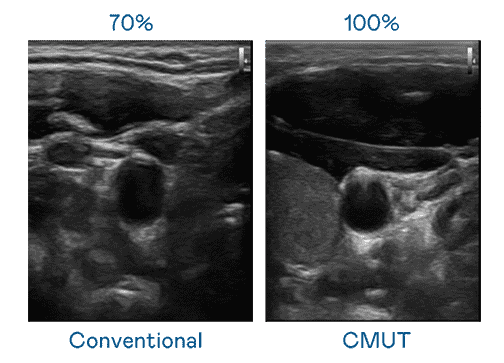

CMUT 技术是一种用电容式微机电元件来产生超音波讯号的技术。。与传统 PZT 压电式技术相比,,CMUT 频宽增加 30%,,,,更宽频的超音波讯号让影像解析度大幅提升,,,,是实现高影像品质医疗超音波扫描、、、、促进精准医疗发展的关键技术。。。。

大频宽带来超清晰影像

超音波影像的解析度高低,,,首先取决于探头能发出的讯号频宽。。。。壹号平台 CMUT 可提供高清晰的超音波讯号,,提供高频宽、、、、高灵敏度、、、、影像纹理细节更高的超音波影像,,,协助医护人员缩短影像判读时间及利用精准的医疗影像进行诊断。。。。